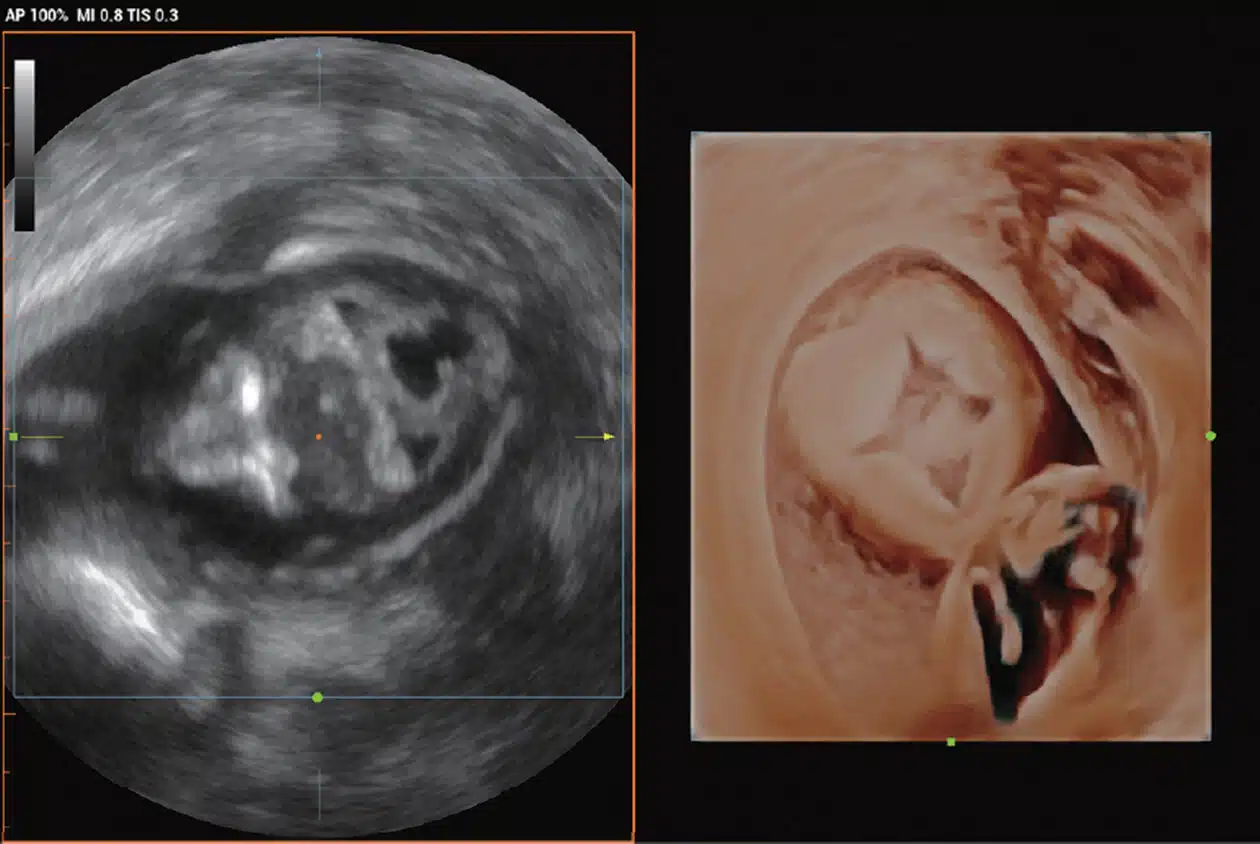

• Early-OB-fetus-with-iLive_Imagyn-I9.jpg

Early OB Fetus Displaying iLive with Hyaline